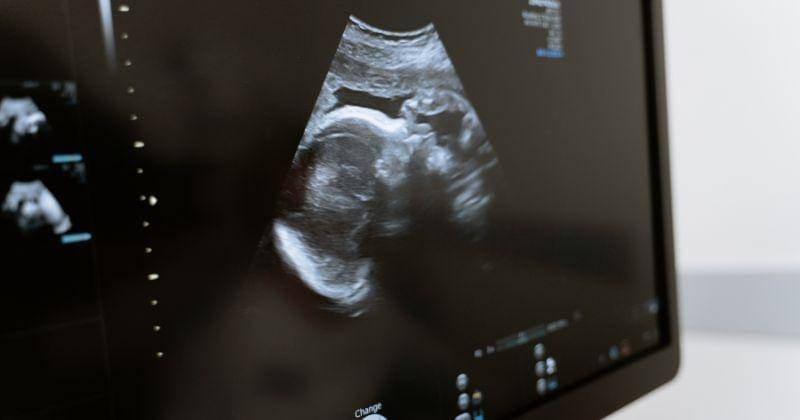

Bahkan, apabila terlalu dini untuk melakukan pemeriksaan USG, Mama tidak jarang tidak mendapati janin tampil di layar USG.

Oleh karena itu, dr. Keven Tali yang merupakan Spesialis Obstetri dan Ginekologi menjelaskan bahwa janin beserta detak jantungnya kerap baru dapat dideteksi pada minggu ke-8 kehamilan.

Saat trimester pertama, pemeriksaan USG pertama kali kerap hanya menampilkan yolk sac atau kantong kuning telur. Kantong tersebut merupakan membran yang membungkus kuning telur untuk diserap oleh embrio yang sedang berkembang.

Kondisi tersebut biasanya dideteksi sejak usia kehamilan 5 minggu. Setelahnya, barulah janin dan detak jantung dapat dideteksi mulai minggu ke-8.

Meskipun demikian, pemindaian yang dilakukan saat pemeriksaan USG belum tentu mendapatkan janin dengan mudah tampil sebab visibilitas kehamilan pada trimester awal dipengaruhi indeks massa tubuh (IMT) mama dan posisi bayi.